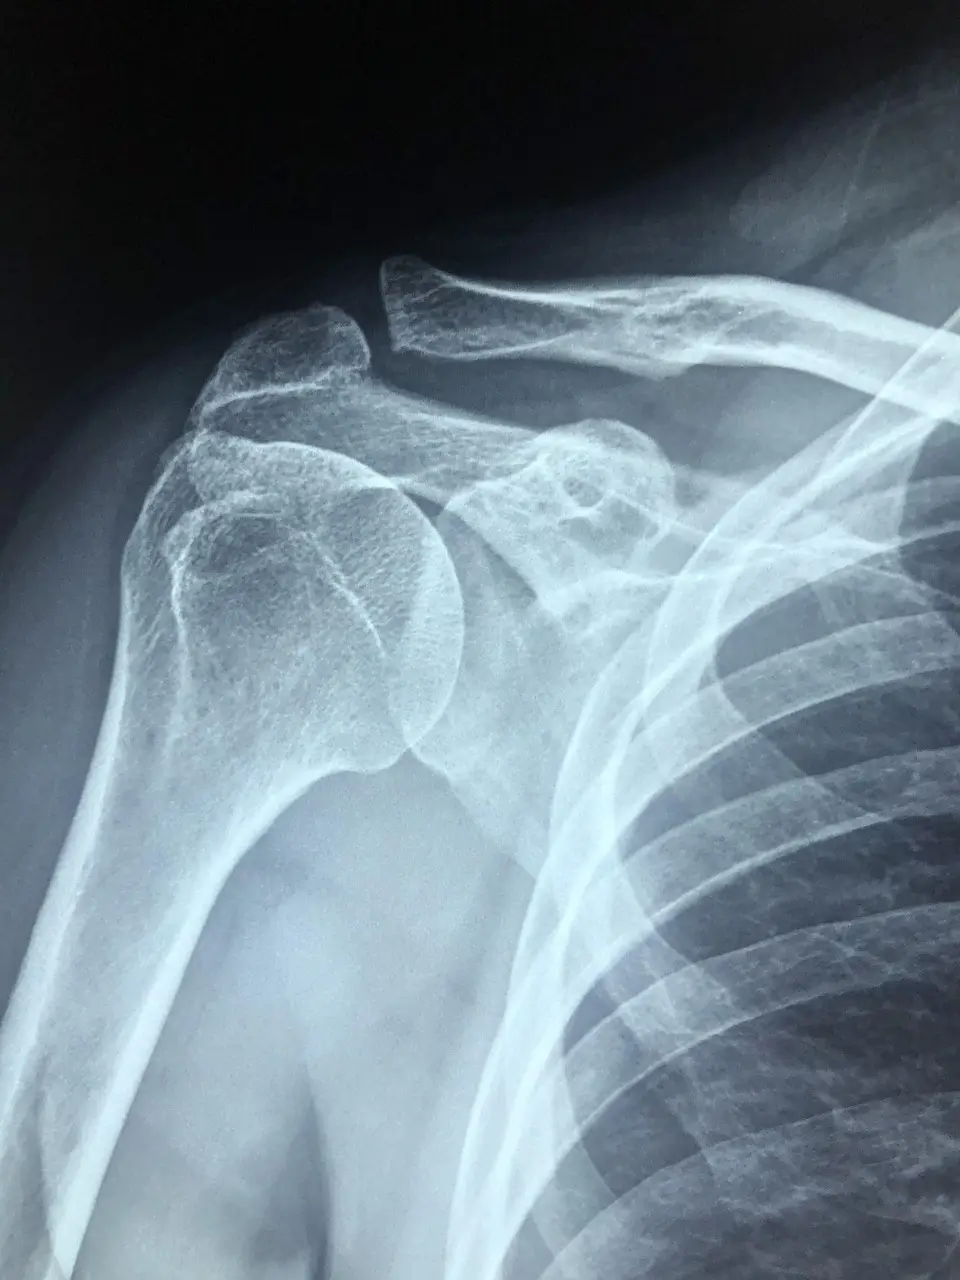

어깨석회화건염은 어깨 관절을 움직이는 힘줄(특히 회전근개)에 칼슘 침착이 생겨 염증과 통증을 유발하는 질환입니다. 처음에는 뻐근한 느낌만 들지만, 점차

특히 40~60대 여성에게 흔하며, 반복적인 팔 사용, 노화, 호르몬 변화, 혈류 문제 등이 원인으로 지목됩니다.

✅ 중요한 점은, 석회가 있다고 무조건 수술이 필요한 건 아니라는 사실입니다. 많은 경우 적절한 치료운동과 물리치료만으로도 충분히 호전될 수 있습니다.